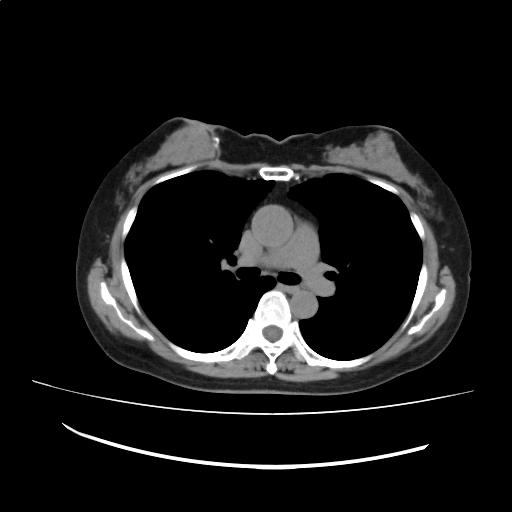

CTスライス1

(Findings)

肺野に明らかな腫瘤性病変および活動性炎症像を認めない。

縦隔および肺門にリンパ節の病的腫大を認めない。

胸水を認めない。

右乳腺に小石灰化を認める。

右乳腺は腫瘤様にみえるが、前回検査と比較して著変は認めない。乳腺病変については、超音波検査やマンモグラフィによる評価が望まれる。

(Impression)

前回検査と比較して著変はない。

CT画像173

(171/198)